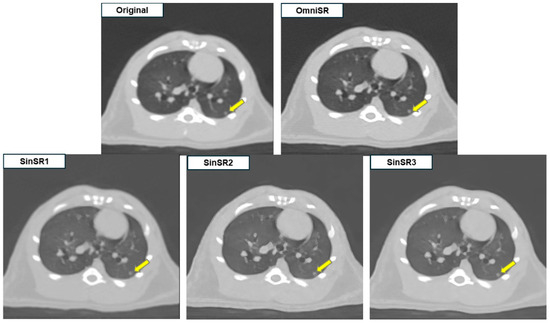

| Margin of lesions | R1 | 4.07 ± 0.73 | 1.09 ± 0.32 | 1.10 ± 0.33 | 1.81 ± 0.90 | N/A |

| R2 | 3.88 ± 0.76 | 1.09 ± 0.32 | 1.10 ± 0.33 | 1.75 ± 0.82 | N/A | |

| Mean | 3.97 ± 0.75 | 1.09 ± 0.32 * | 1.10 ± 0.33 *† | 1.78 ± 0.86 *§ | <0.001 | |

| Nodule/mass detectability | R1 | 4.51 ± 0.85 | 1.25 ± 0.66 | 1.25 ± 0.66 | 1.50 ± 0.70 | N/A |

| R2 | 4.40 ± 0.83 | 1.15 ± 0.52 | 1.16 ± 0.53 | 1.67 ± 0.81 | N/A | |

| Mean | 4.46 ± 0.84 | 1.20 ± 0.59 * | 1.20 ± 0.60 *† | 1.58 ± 0.76 *§ | <0.001 | |

| Anatomic structure similarity | R1 | 3.00 ± 0.00 | 1.00 ± 0.00 | 1.00 ± 0.00 | 2.06 ± 0.91 | N/A |

| R2 | 3.00 ± 0.00 | 1.00 ± 0.00 | 1.00 ± 0.00 | 2.20 ± 0.90 | N/A | |

| Mean | 3.00 ± 0.00 | 1.00 ± 0.00 * | 1.00 ± 0.00 *† | 2.13 ± 0.90 *§ | <0.001 | |

| Image noise | R1 | 3.00 ± 0.00 | 3.55 ± 0.50 | 3.55 ± 0.50 | 4.00 ± 0.00 | N/A |

| R2 | 3.00 ± 0.00 | 3.51 ± 0.50 | 3.48 ± 0.50 | 3.80 ± 0.40 | N/A | |

| Mean | 3.00 ± 0.00 | 3.53 ± 0.50 * | 3.51 ± 0.50 *† | 3.90 ± 0.30 *§ | <0.001 | |

| Image artifact | R1 | 3.00 ± 0.00 | 1.67 ± 0.47 | 1.49 ± 0.50 | 1.69 ± 0.47 | N/A |

| R2 | 2.94 ± 0.24 | 1.65 ± 0.48 | 1.53 ± 0.50 | 1.72 ± 0.45 | N/A | |

| Mean | 2.97 ± 0.17 | 1.66 ± 0.48 * | 1.51 ± 0.50 *† | 1.71 ± 0.46 *†§ | <0.001 | |

| Overall image quality | R1 | 4.78 ± 0.42 | 1.66 ± 0.74 | 1.77 ± 0.71 | 3.14 ± 0.79 | N/A |

| R2 | 4.71 ± 0.48 | 1.65 ± 0.73 | 1.76 ± 0.70 | 3.08 ± 0.77 | N/A | |

| Mean | 4.75 ± 0.45 | 1.66 ± 0.73 * | 1.77 ± 0.70 *† | 3.11 ± 0.78 *§ | <0.001 |